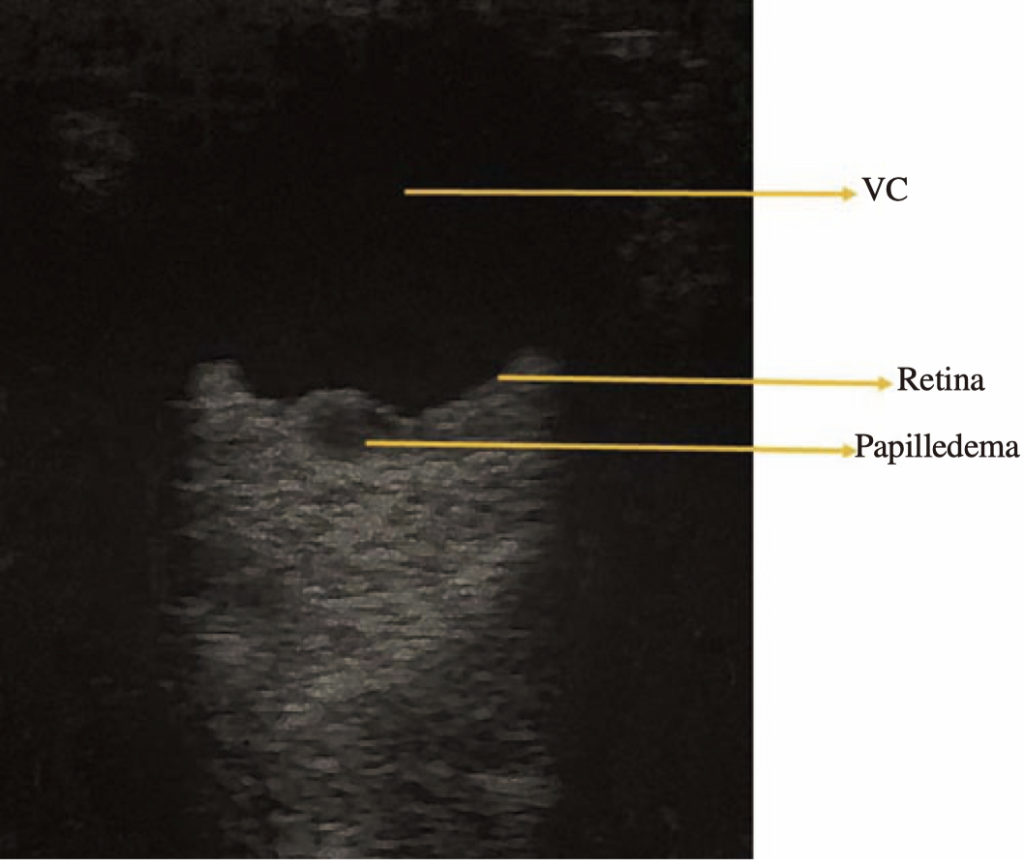

視神経乳頭浮腫(Papilledema)

Builes, Santiago Vasquez, Gonzalez, et al. Using point-of-care ultrasound in ocular emergencies: A mini review. Journal of Acute Disease 9:p 190-193, September 2020. より引用

- 視神経鞘径の拡大が見られる

- 正常値は5mm以下で超えると頭蓋内圧亢進を示唆する